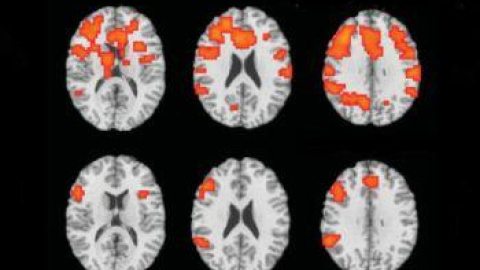

Ha encontrado un aliado en la ciencia. El pasado verano, Hamilton se sometió a una prueba con la última tecnología de resonancia magnética funcional (fMRI o functional magnetic resonance imaging), un revolucionario avance científico para distinguir la verdad de la mentira. La técnica consiste en un escáner de cuerpo entero conectado a micrófonos, altavoces y un teclado de ordenador. El analista interroga al sujeto mientras la cámara del escáner recoge imágenes de la mente.

El profesor Sean Spence, director del experimento practicado en Hamilton, explica: “Cuando utilizas fMRI, el escáner detecta cambios en las propiedades magnéticas de la sangre. Los estudios realizados hasta la fecha coinciden en sugerir que cuando una persona miente, la mente envía más sangre al área ventrolateral del cortex. Se detecta más actividad en esa zona”.

Este profesor de psiquiatría general reconoce que su investigación “no prueba que Hamilton sea inocente, pero sí demuestra claramente que su mente responde como si fuera inocente”. Dedujo esta conclusión de las distintas reacciones detectadas por el escáner cada vez que la mujer explicaba su versión de los hechos y respondía a las opiniones de la acusación. “Le hicimos cuatro escáneres y las respuestas fueron siempre consistentes con su versión de la verdad”, confirma.